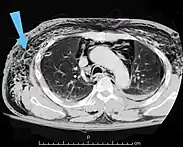

![]() | |

| An abdominal CT scan of a patient with subcutaneous emphysema (arrows) | |